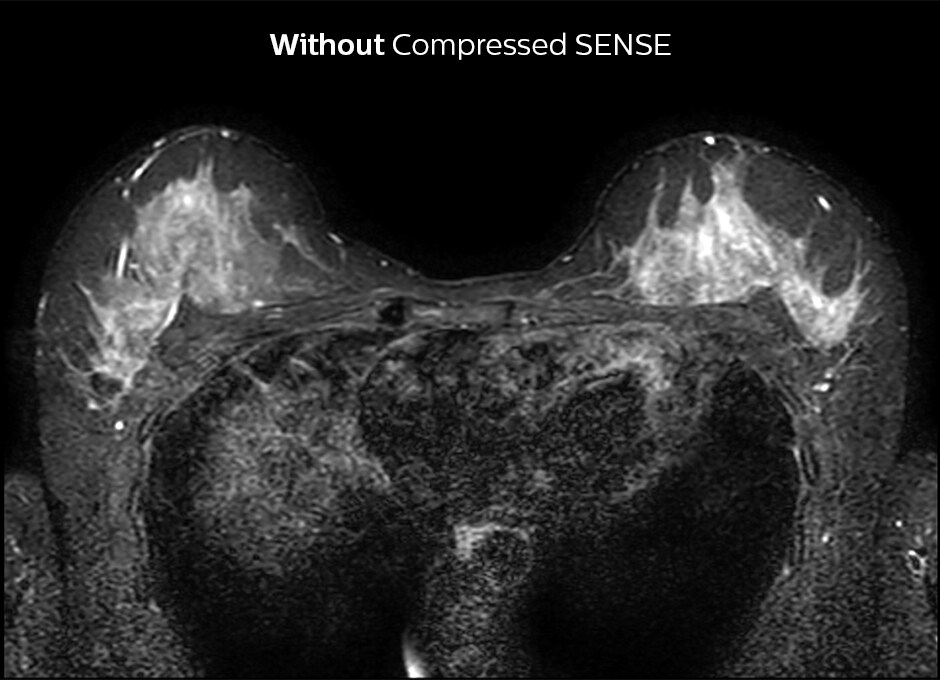

In het KSW-ziekenhuis wordt Compressed SENSE ook toegepast om de scantijd bij een MRI onderzoek van de borsten te verkorten. 2D STIR is nu sneller en sequenties die silicone zichtbaar maken zijn bijvoorbeeld 30% sneller. De post-contrast 3D T1 THRIVE kan met ongeveer 40% worden versneld en Compressed SENSE wordt momenteel toegevoegd aan de dynamische T1-sequentie om een hogere resolutie te krijgen in dezelfde scantijd.